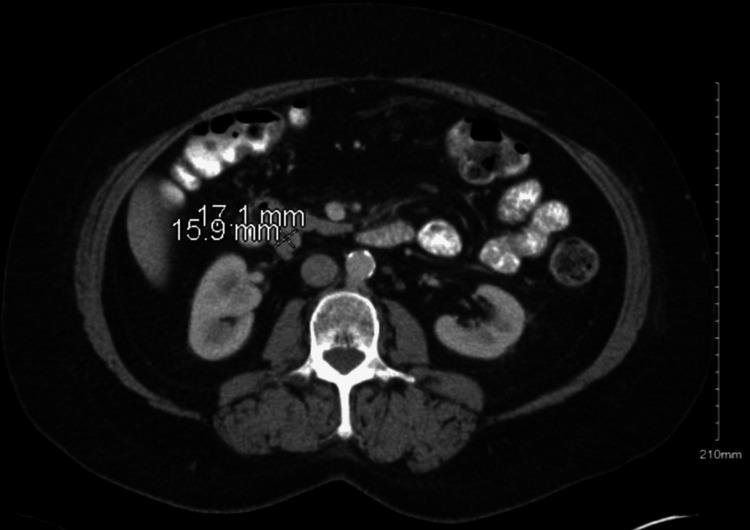

Imatinib, a tyrosine kinase inhibitor, is widely used for treating gastrointestinal stromal tumors (GISTs) and chronic myeloid leukemia (CML). While commonly associated with mild fluid retention, significant pleural effusion is an uncommon but potentially serious adverse effect. We present a case of recurrent pleural effusions secondary to imatinib therapy in a 62-year-old female patient with metastatic lung adenocarcinoma and a concurrent GIST harboring an exon 9 mutation. She was initiated on imatinib 400 mg daily, later increased to twice daily. Within weeks, she developed progressive dyspnea, and imaging revealed large bilateral pleural effusions. Pleural fluid analysis demonstrated an exudative effusion, with cytology and microbiological studies ruling out infection or malignancy. Cardiac function was preserved, and there were no signs of volume overload. She underwent multiple thoracenteses for symptomatic relief. Due to recurrent pleural effusions, imatinib was permanently discontinued, leading to complete resolution of the effusions. Subsequent treatment with sunitinib was not tolerated due to severe mucositis and cytopenias. Despite discontinuation of targeted therapy, both her GIST and metastatic lung cancer remained stable under surveillance. While pleural effusions are frequently reported with dasatinib, they are rare with imatinib. The proposed mechanisms include inhibition of platelet-derived growth factor receptors (PDGFRs), leading to increased vascular permeability, impaired lymphatic drainage, and renal sodium retention. Dose reduction may mitigate fluid retention; however, our patient developed significant pleural effusions at standard dosing, necessitating treatment discontinuation. This case underscores the importance of recognizing pleural effusion as a rare but serious adverse effect of imatinib therapy. Clinicians should maintain a high index of suspicion for drug-induced pleural effusions, particularly in the absence of other etiologies, and consider discontinuation if clinically indicated. Early recognition and management can prevent complications and improve patient outcomes.

伊马替尼是一种酪氨酸激酶抑制剂,广泛用于治疗胃肠道间质瘤(GIST)和慢性粒细胞白血病(CML)。虽然通常与轻度液体潴留有关,但大量胸腔积液是一种罕见但可能严重的不良反应。我们报告一例62岁女性患者,患有转移性肺腺癌和同时存在外显子9突变的GIST,因伊马替尼治疗继发反复胸腔积液。她开始每天服用400毫克伊马替尼,后来增加到每天两次。几周内,她出现进行性呼吸困难,影像学检查显示双侧大量胸腔积液。胸腔积液分析显示为渗出性积液,细胞学和微生物学研究排除了感染或恶性肿瘤。心脏功能保持正常,没有容量超负荷的迹象。她接受了多次胸腔穿刺以缓解症状。由于反复出现胸腔积液,伊马替尼被永久停用,积液完全消退。随后使用舒尼替尼治疗因严重粘膜炎和血细胞减少而无法耐受。尽管停用了靶向治疗,但在监测下她的GIST和转移性肺癌均保持稳定。虽然达沙替尼经常报告有胸腔积液,但伊马替尼引起的则很少见。推测的机制包括抑制血小板衍生生长因子受体(PDGFR),导致血管通透性增加、淋巴引流受损和肾钠潴留。减少剂量可能减轻液体潴留;然而,我们的患者在标准剂量下出现了大量胸腔积液,需要停药。该病例强调了认识到胸腔积液是伊马替尼治疗罕见但严重的不良反应的重要性。临床医生应高度怀疑药物性胸腔积液,特别是在没有其他病因的情况下,并在临床指征明确时考虑停药。早期识别和管理可以预防并发症并改善患者预后。